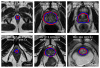

This paper proposes a method for segmenting the prostate on magnetic resonance (MR) images. A superpixel-based 3D graph cut algorithm is proposed to obtain the prostate surface. Instead of pixels, superpixels are considered as the basic processing units to construct a 3D superpixel-based graph. The superpixels are labeled as the prostate or background by minimizing an energy function using graph cut based on the 3D superpixel-based graph. To construct the energy function, we proposed a superpixel-based shape data term, an appearance data term, and two superpixel-based smoothness terms. The proposed superpixel-based terms provide the effectiveness and robustness for the segmentation of the prostate. The segmentation result of graph cuts is used as an initialization of a 3D active contour model to overcome the drawback of the graph cut. The result of 3D active contour model is then used to update the shape model and appearance model of the graph cut. Iterations of the 3D graph cut and 3D active contour model have the ability to jump out of local minima and obtain a smooth prostate surface. On our 43 MR volumes, the proposed method yields a mean Dice ratio of 89.3 ±1.9%. On PROMISE12 test data set, our method was ranked at the second place; the mean Dice ratio and standard deviation is 87.0±3.2%. The experimental results show that the proposed method outperforms several state-of-the-art prostate MRI segmentation methods.